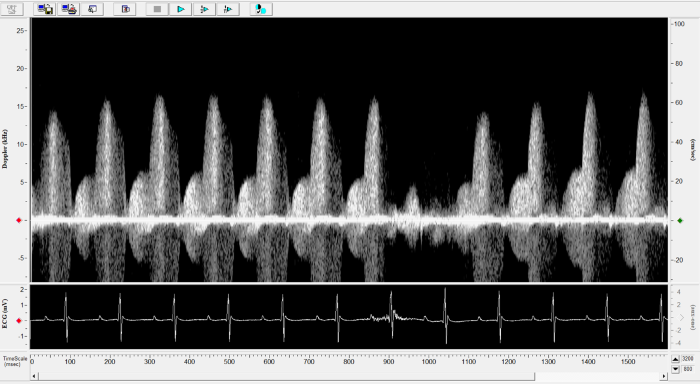

Imaging gallery - Doppler Flow Velocity System

Renal Flow. Image Credit: Scintica Instrumentation Inc.